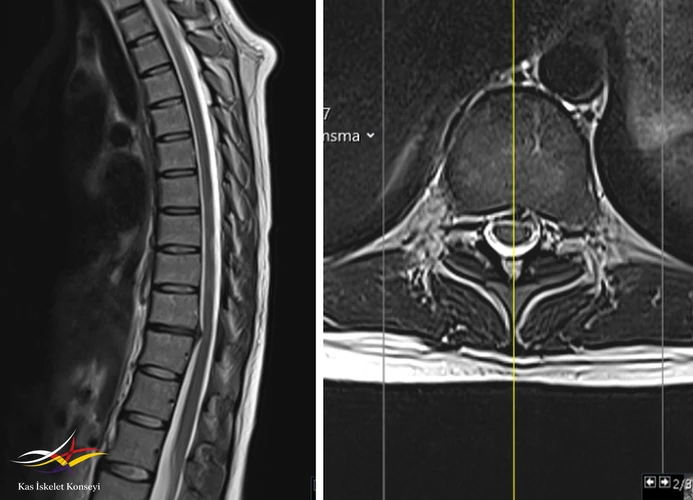

İncelemeler: HLA B27 negatif. Torasik MRG: Alt dorsal seviyede disk hernisi mevcut. Belirgin bir nöral bası yok.

Resim 1. Torasik MRG alt torasik seviyede santral diskal bulgingi gösteriyor. Diskin hipointens görünümü dejenerasyonla uyumludur.